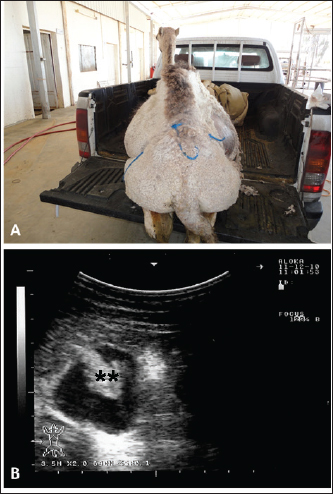

Full details including presenting complaints, symptoms, diagnosis, treatment, and outcome of the 25 dromedary camels with depraved appetites are listed in Table 1. The dromedary camels with depraved appetites had different presentations, but all of the examined animals had a history of eating foreign or inanimate objects. Pica was evident in some cases upon initial clinical examination (Fig. 1). Twelve of the camels (48%) were admitted with a history of loss of body weight and 8 (32%) with partial or complete loss of defection. Seven out of the nine (77.8%) lactating camels in this study suffered from decreased milk production. An example of such a case is shown in Figure 2. In animals undergoing laparotomy, the foreign bodies were surgically removed as shown in Figure 3. Bouts of repeated vomiting were also found in 5 (20%) of the camels. In animals that underwent rumenotomy, the foreign bodies were removed as in Figure 4. Eating feces (coprophagia) was also found in six camels as shown in Figure 5. Sixteen (64%) of the camels were recovered while the remaining 9 (36%) did not survive.

Fig. 4. Pica in a female camel referred with a history of depraved appetite and repeated volition (A). Exploratory rumenotomy revealed wool balls, plastics, and robes within the rumen (B).

Sonographic and postmortem findings are summarized in Table 2. In cases of camels presented with a history of pica and with decreased or total absence of feces, the obstructing foreign body was imaged in 10 of the 25 camels (40%) occluding completely or partially the intestines that may be confirmed at abdominal surgery (Figs. 2, 3, and 6). Foreign bodies within the rumen could not be visualized with ultrasound owing to the gas content. In cases where the rumen is impacted by sand, small pin-points revealing acoustic enhancement were imaged in 5 (20%) of the camels. An example of these cases is shown in Figure 7. Foreign bodies were removed from the rumen or intestines at exploratory rumenotomy and laparotomy, which included plastics, cloths, sand, mud, robes, wool balls, glasses, or even metallic objects that were blunt or sharp (Figs. 8 and 9).

Fig. 8. Pica in two female camels with a history of reduced feed intake and weight loss. Exploratory rumenotomy revealed large amounts of plastics, cloths, and robes in the image (A), and plastics and robes in image (B).